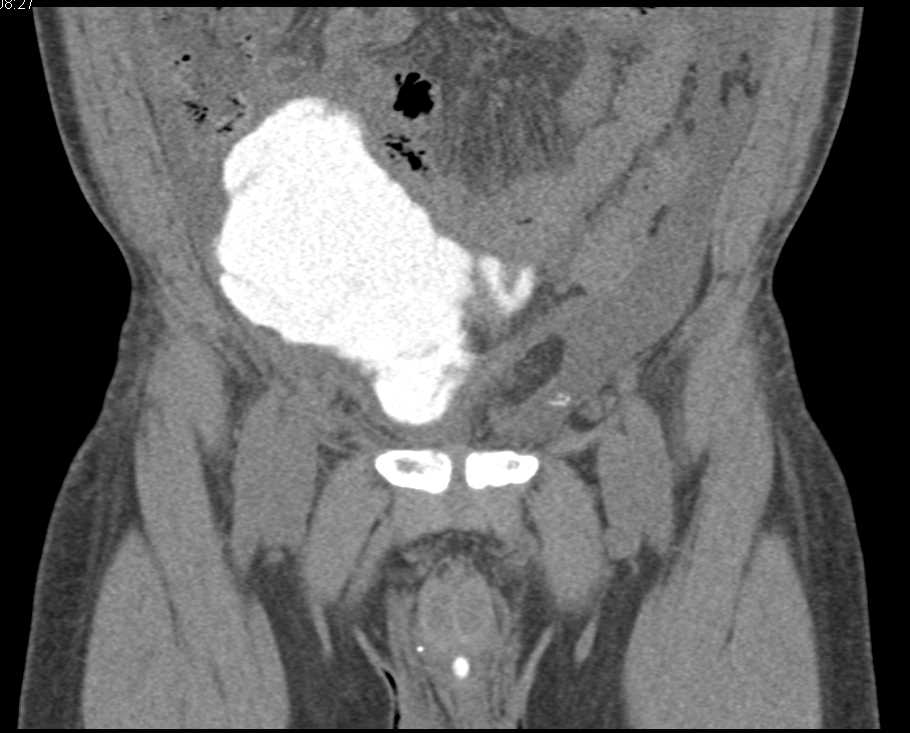

Bladder Cancer with Adenopathy